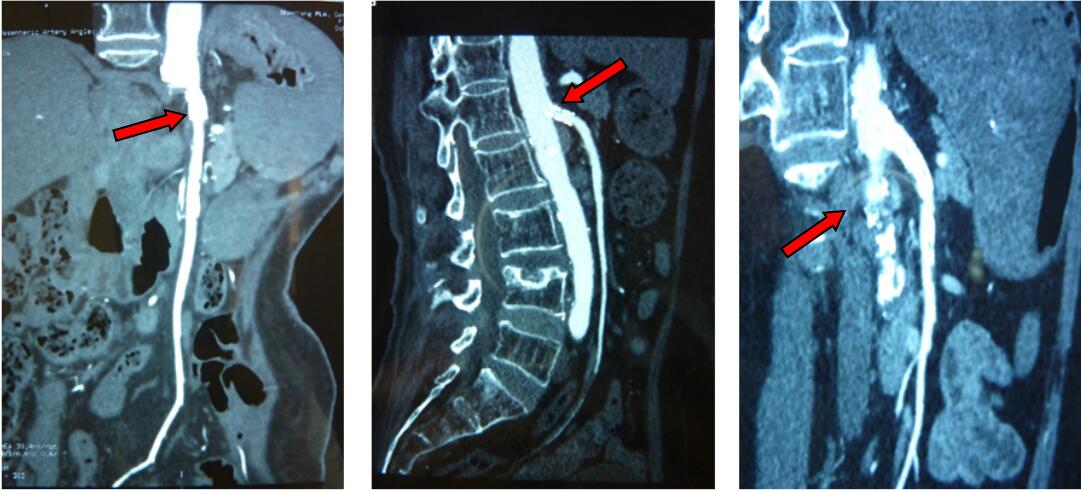

6.2 影像学检查(插入AMI的典型CTA影像,图 2)

| 图 2 CTA下肠系膜血管病变 |

目前,CTA成像技术已正式取代了血管造影作为影像学首选检查(图 2)。

AMI病情进展的情况下,CTA可提示肠道不可逆的缺血(肠道扩张和肠壁增厚,内脏增强影像的减弱甚至消失,肠壁及门静脉积气等)和腹腔内存在的游离气体[2]。对于NOMI的患者而言,CTA可能提示肠道缺血并在肠系膜血管周围显示出游离气体。而在VAMI患者中,静脉相CTA甚至可直接提示肠系膜上静脉血栓[21]。此外,VAMI的相关表现还包括肠壁增厚,积气,脾大和腹水等。